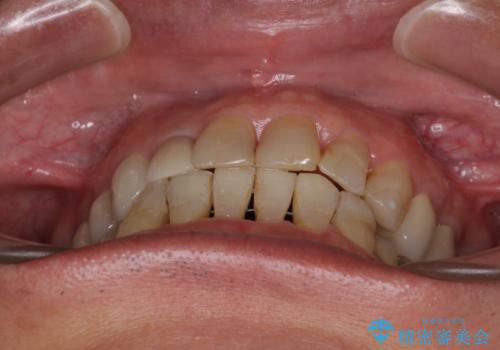

治療後には咬みやすさだけでなく、前歯が大変審美的に仕上がり、患者様には大変満足していただきました。